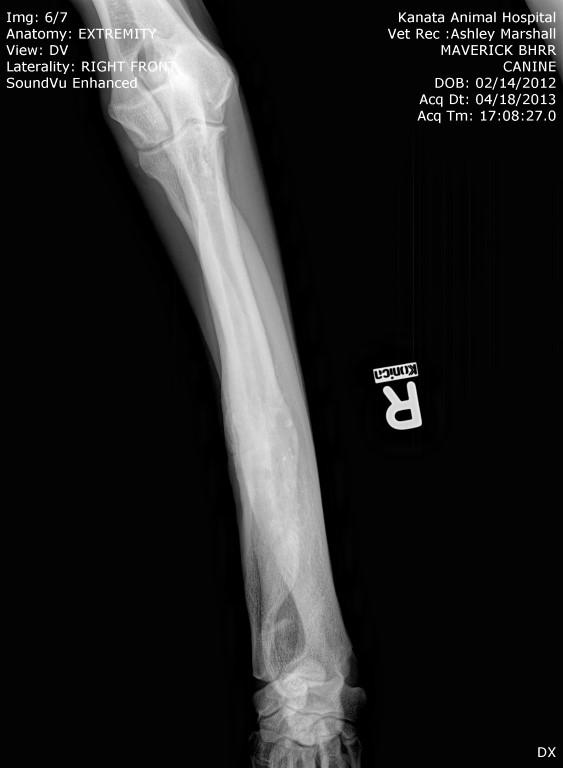

His surgery to remove the implant on his left front leg after a sudden rejection/infection with the plate screws was on September 24th. This is his fourth leg surgery. He had two surgeries on his front legs which were deformed when he first arrived to BHRR and then now he has had to have two more surgeries due to reacting to the Implants.

It does appear that I may well be correct that after 2 years and four months plus from first having the original leg surgery, he is now rejecting this implant. He had this leg first operated on in July 2013. frown emoticon

Here is a photo of his foot tonight. The edema is all over the leg, into his chest and his one lymph node is huge. The vet reviewed his x-Rays taken on Friday and saw a darker area on the one bone, not the one with the plate/screws and wants the ortho specialist to take a closer look.

BHRR’s Mavie, for those who are not familiar with his journey has had two surgeries on his front legs, ended up reacting to the fixator on the left front leg, then last November rejected the implant in the right front leg and now, is having symptoms very similar on the left front leg.

Sadly, BHRR’s Maverick began to suddenly favour the left front leg that has the remaining implant in it last night. As of this AM, he was not weight bearing and though he did not have a fever, it was a bit warm and swollen and he was brought into KAH.

As many are aware, in November of 2014, BHRR’s Maverick, had a violent aggressive reaction to the implant in his right front leg and had to spend several months on strong antibiotics, had to have an emergency surgery to remove the plate/screws and was treated for a terrible abscess from reacting to the implant. His ortho specialist even cultured the implant to see what may be brewing on it…..

How it started with his right leg is how his left leg is now ‘appearing’ to be.